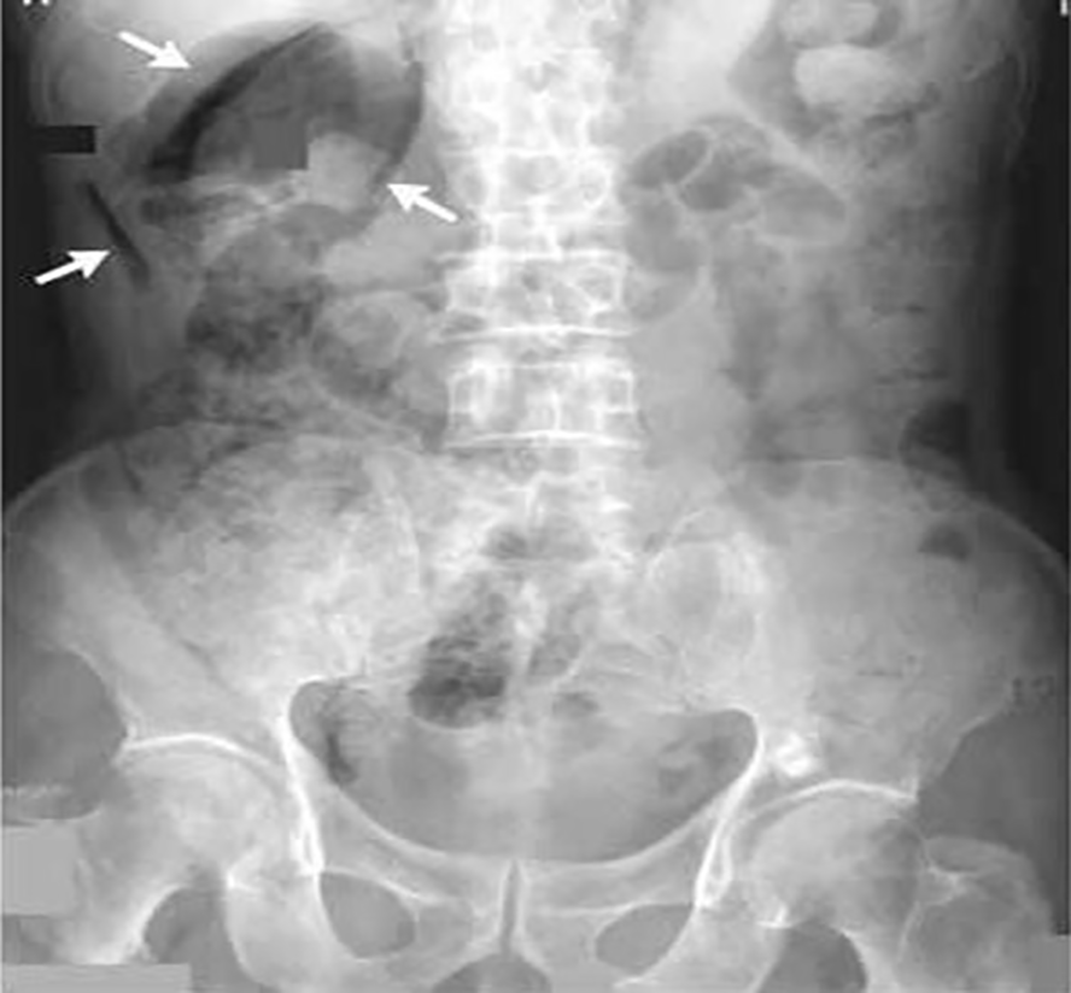

Thus, in light of the objective findings, a clinical suspicion of acute appendicitis was raised, and the patient was investigated accordingly. Laboratory tests showed an increase of inflammation markers (WBC 24.900/mm^3, CRP 15.3 mg/dL), elevated serum amylase (1737 UI/L), and elevated serum creatinine (2.76 mg/dL). Lactate levels were in the range (1.2 mmol/L). An abdominal CT scan with contrast medium was performed, which showed the presence of abscess collections in the right pararenal space, in communication with perihepatic effusion and with some collections close to the appendiceal worm (no intra-abdominal free air), that is to say a radiological picture highly suspicious for acute perforated appendicitis with involvement of the retroperitoneum. On completion, a chest x-ray was also carried out, which showed a slight pleural effusion on the right side.

Since the clinical, laboratory and radiological findings were compatible with acute appendicitis, it was decided to have the patient undergo laparoscopic appendectomy: surgical exploration revealed severe choleperitonitis, with the presence of bile fluid both intra and retroperitoneally, in particular in the right renal lodge, right parietocolic region and in the supra and subhepatic area. Furthermore, a picture of widespread adhesions was found in which the hepato-biliary-pancreatic region was engulfed by inseparable adhesions which made exploration of the duodenal region difficult. The appendix was visualized and did not appear to be affected by acute inflammation. Hence, an intraoperative diagnosis of diffuse biliary peritonitis due to a probable perforation of a posterior duodenal ulcer was made ( Figure 1). Given the patient’s age and the severity of the clinical and surgical condition, characterized by the presence of inseparable adhesions (probably the result of previous surgery for peptic ulcer), it was decided to postpone further surgical procedures, except for drainage of the subhepatic lodge. At the end of the procedure, two abdominal drains are placed: one in the subhepatic compartment and the other in the hypogastrium. Finally, a methylene blue test was performed, which was present in both drains. A nasogastric tube and urinary catheter were left in place.

From a physiopathological point of view, VS arises when the biliary enteric fluid leaks from the perforated ulcer through the right parietocolic gutter, reaching the right iliac fossa, causing a localized chemical peritonitis with consequent positive McBurney.10 For this reason, in some cases, the pain can be of a migratory type from the periumbilical/epigastric region to the RLQ, sometimes with a sudden onset and worsening, otherwise with a slower progression and lasting a few days.10 Blood tests may show an increase in serum amylase and lipase.11 Abdominal CT scan can also allow visualization of small amounts of free intra-abdominal gas: in addition to peritoneal and retroperitoneal effusions, it is possible to detect pneumoperitoneum (gastric ulcer), pneumo-retroperitoneum (duodenal ulcer), particularly posterior to the right kidney (the “veiled right kidney sign”, Figure 2)12 and sometimes thickening of the gastric/duodenal wall. However, it is not always possible to visualize the exact location of the perforation. PPU can be treated “conservatively” (fasting, nasogastric tube, i.v. antibiotics and PPI) so as to promote spontaneous healing of the ulcer after a period of observation, which will be confirmed with water-soluble contrast imaging.6 Alternatively, it can be treated with surgery (laparoscopically or laparotomically), using various possible surgical techniques (depending on the characteristics of the ulcer and the patient), among which we mention: gastroraphy (with or without omentoplasty), Graham’s repair (free omental Graham’s patch) or Cellan-Jones repair (pedicled omentoplasty).13 In case of lesions >2 cm, nevertheless, gastric resection may be necessary.13